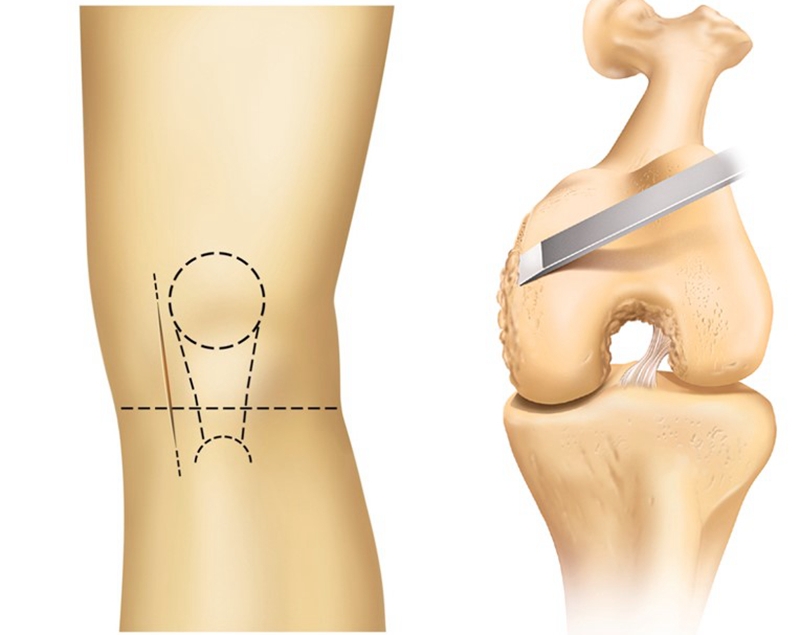

切口:内侧微创切口,从髌骨内侧缘至内侧胫骨结节。

胫骨垂直截骨:内外定位、旋转定位。注意第一刀非常重要,直接决定假体位置。

垂直截骨内外定位:垂直截骨位置位于内侧棘顶端的内侧,在股骨髁外侧2到3mm处,紧贴ACL足印区内侧。

紧沿胫骨脊最高处内侧,不要截骨过深。

垂直截骨旋转定位:往复锯指向髂前上棘,即轻微内旋。